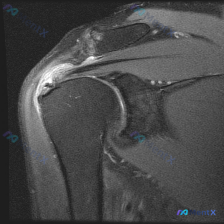

整理了一份肩部MRI病例讨论材料,医生的核心问题是排查盂唇病变,但看影像发现了一些矛盾点。先放MRI T2序列冠状位的分析: 1. 骨性结构:肱骨头、肩峰及锁骨远端轮廓尚可,未见骨折线或骨髓水肿 2. 肌腱与肩袖:冈上肌腱在肱骨大结节止点处形态异常,连续性中断,T2高信号 3. 关节与滑囊:肩峰下-...

最近整理了一份肩部MRI的病例讨论材料,患者主要问题是肩部疼痛,但问题明确指向"盂唇病变"范畴。先看T2冠状位图像的关键发现: 1. 冈上肌腱在肱骨大结节止点处有显著高信号,连续性可能中断 2. 肩峰下-三角肌下滑囊有明显的高信号积液 3. 关节盂唇区域信号存在改变 大家觉得这个病例更符合哪种诊断?...

整理了一个肩关节MRI-T2序列冠状位的病例讨论材料,医生提问关注盂唇病变,但影像最突出的是冈上肌腱全层撕裂。这份病例的核心疑问点和影像发现存在一定不匹配,大家第一眼怎么看?

看到一个肩部MRI(冠状位)的病例资料,用户最初的问题是关于「盂唇病理」,但整理的分析报告里有几个点挺值得讨论的: 先放影像的关键发现: - 冈上肌腱连续性中断,断端回缩,伴冈上肌肌腹萎缩、脂肪浸润 - 肩峰下-三角肌下滑囊积液,肩峰下间隙变窄,肱骨头上移 - 肱骨头大结节下方骨髓水肿 - 盂唇形态...